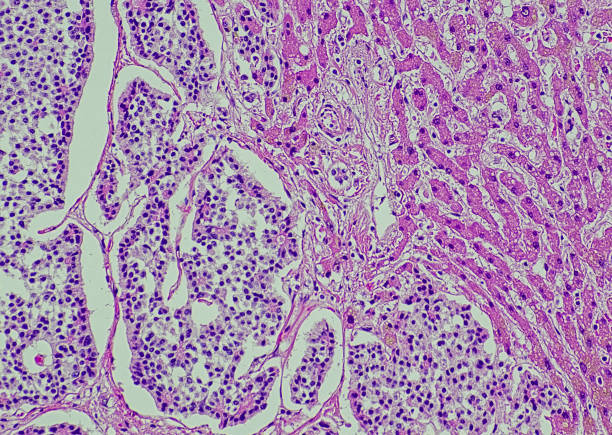

간암 초기증상 10가지 총정리

간암은 초기에는 증상이 뚜렷하지 않아서 많은 경우 발견이 어려울 수 있습니다. 그러나 조기 발견과 치료가 가능하다면 생존률을 높일 수 있으므로 간암 초기 증상을 알아두는 것이 중요합니다. 다만, 이미 간암 초기증상들이 나타나는 경우는 이미 간에서 분해 및 대사되어 처리되는 독성 물질들이 쌓이면서 발생할 수 있어 빠른 조치를 해야 하며 이를 위하여 이번 시간에는 간암 초기증상에 대해 자세히 알아보겠습니다.